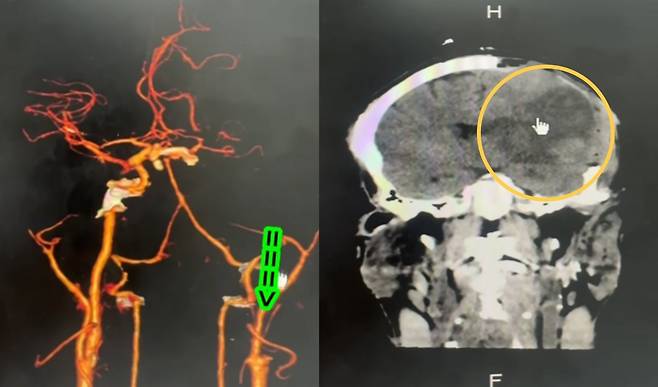

병원에 도착했을 때는 이미 뇌 손상이 진행된 상태였다. CT 검사 결과, 왼쪽 뇌는 이미 산소 부족으로 괴사한 상태였다. 또 경동맥(목에서 뇌로 가는 큰 혈관) 두 곳이 손상된 것으로 확인됐다.

마사지로 인해 혈관이 파열됐고, 혈전이 생겨 혈류를 막아버린 것이다. 그 결과 뇌에는 8시간 동안 혈액이 공급되지 않았다. 이후 경동맥 손상은 순식간에 뇌졸중으로 이어졌다. 남성은 결국 사망했다.